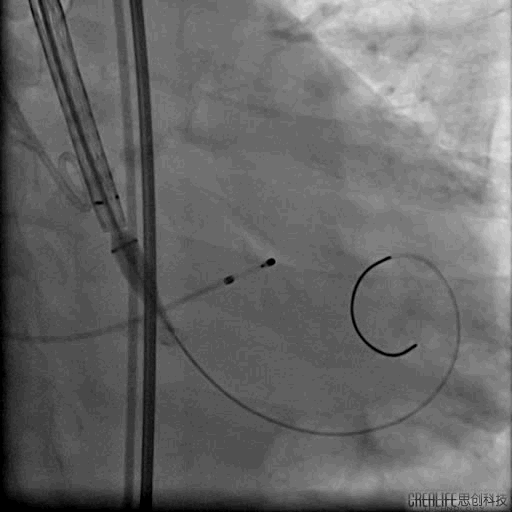

球囊跨二尖瓣

24MM二尖瓣球囊扩张